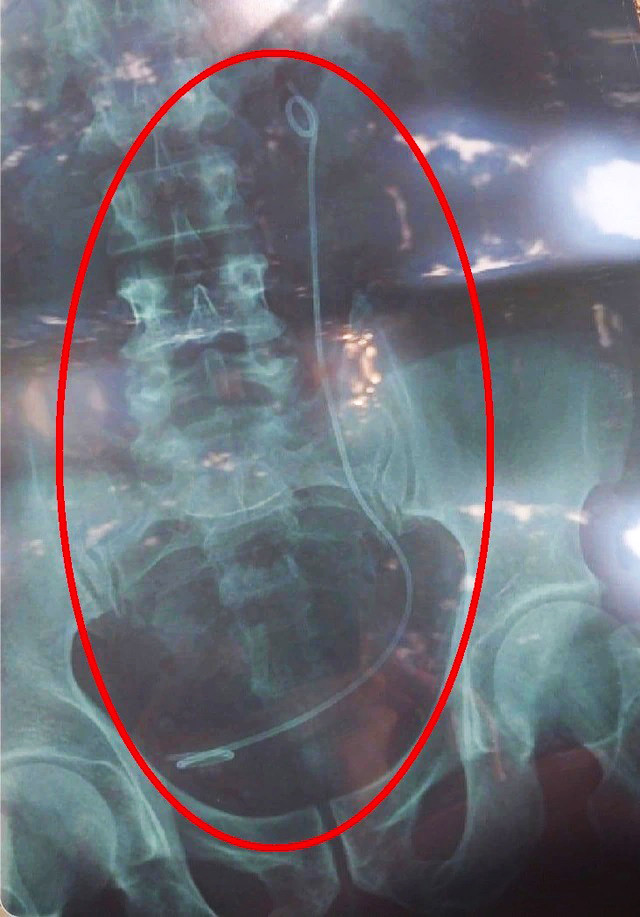

| Phim chụp X-quang có sợi dây trong ổ bụng là của bệnh nhân khác nhưng trao nhầm cho ông H. |

Sáng 20/2, bác sĩ ở Bệnh viện Đa khoa Lâm Đồng yêu cầu ông H. đi chụp X-quang. Sau khi nhận kết quả, bác sĩ thông báo trong bụng ông H. có 1 sợi dây ống và tư vấn làm thủ thuật nội soi để lấy sợi dây này ra.

Tuy nhiên, sau khi tiến hành nội soi, ê-kíp thực hiện không tìm thấy đoạn ống nhựa như phim X-quang thể hiện. Lúc này, bộ phận chức năng tiến hành rà soát phát hiện người của bệnh viện đã đưa nhầm kết quả chụp X-quang của một bệnh nhân khác cho ông H..